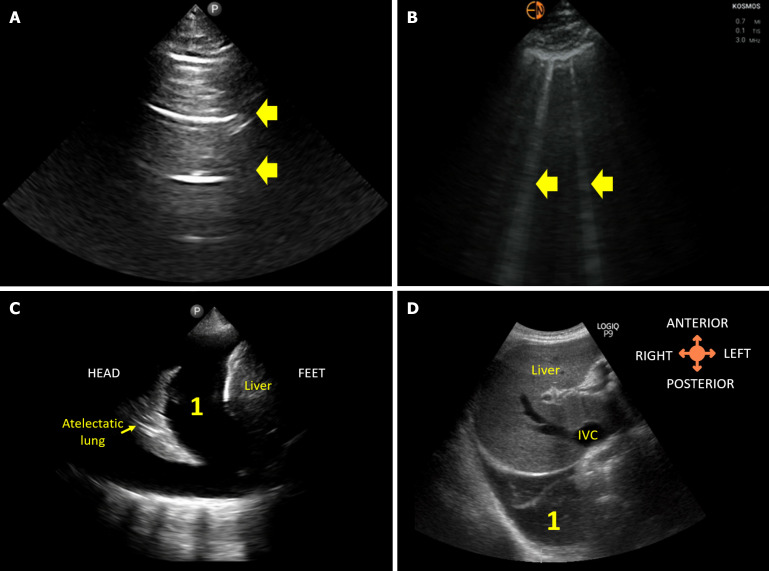

Discerning the etiology of acute kidney injury (AKI) in cirrhotic patients remains a formidable challenge due to diverse and overlapping causes. The conventional approach of empiric albumin administration for suspected volume depletion may inadvertently lead to fluid overload. In the recent past, point-of-care ultrasonography (POCUS) has emerged as a valuable adjunct to clinical assessment, offering advantages in terms of diagnostic accuracy, rapidity, cost-effectiveness, and patient satisfaction. This review provides insights into the strategic use of POCUS in evaluating cirrhotic patients with AKI. The review distinguishes basic and advanced POCUS, emphasizing a 5-point basic POCUS protocol for efficient assessment. This protocol includes evaluations of the kidneys and urinary bladder for obstructive nephropathy, lung ultrasound for detecting extravascular lung water, inferior vena cava (IVC) ultrasound for estimating right atrial pressure, internal jugular vein ultrasound as an alternative to IVC assessment, and focused cardiac ultrasound for assessing left ventricular (LV) systolic function and identifying potential causes of a plethoric IVC. Advanced POCUS delves into additional Doppler parameters, including stroke volume and cardiac output, LV filling pressures and venous congestion assessment to diagnose or prevent iatrogenic fluid overload. POCUS, when employed judiciously, enhances the diagnostic precision in evaluating AKI in cirrhotic patients, guiding appropriate therapeutic interventions, and minimizing the risk of fluid-related complications.